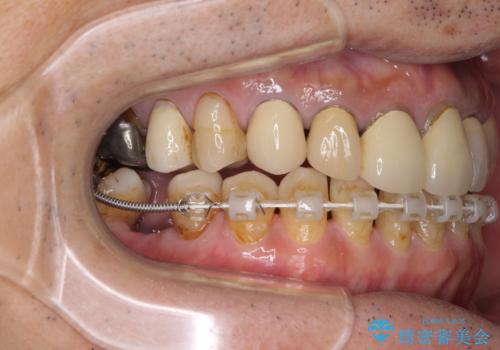

また、下顎前歯にはスペースがあり、コンポジットレジンでスペースを閉じている状態だったので、前歯のスペースを解消しつつ、奥歯にスペースを獲得するよう矯正治療を行うこととしました。

並行して左下にはインプラントを埋入し、上顎臼歯部の気になる部分も根管治療などを進めて行き、矯正治療を終えると同時に補綴治療を行うこととしました。

奥歯1歯分を動かすには時間がかかるため、矯正治療には思いの外時間がかかりました。

痛みのある奥歯は必要に応じて根管治療を行い、左下インプラントは角化歯肉の移植により清掃性を向上させ、気になっていた部分をしっかりと改善させることができました。